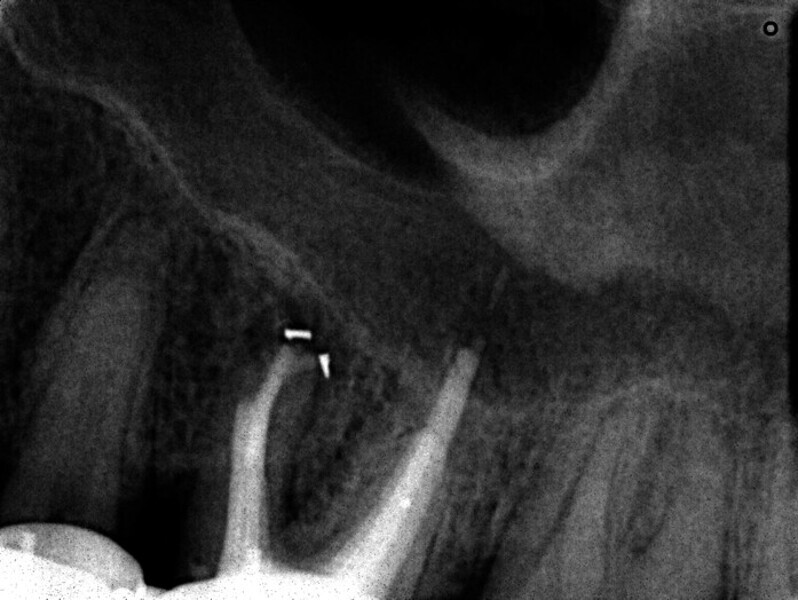

Maxillary sinus and root canal therapy complications